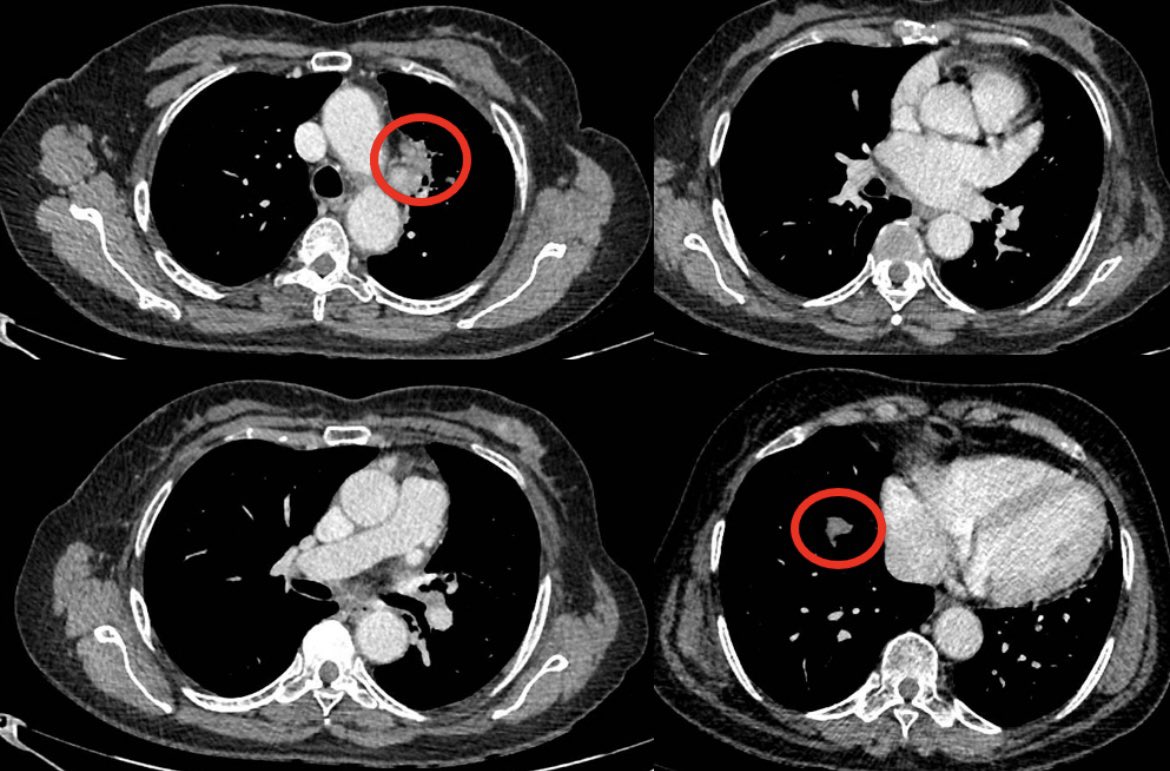

The patient with a broken heart.

Pt in mid 60s with past smoking history presented with chest discomfort and dyspnea

Evaluation with CTA showed no PE but demonstrated a very large LUL mass with direct extension into mediastinum and L atrium and additional R sided lung lesions c/w st4 disease

Cardiac MR and ECHO confirm a mobile mass in L atrium contiguous w LUL mass

Path shows lung adenoca, PD-L1 TPS score >90%, ctDNA+ for K-Ras G12C

Tumor board review: surg/IR interventions not feasible, XRT likely not safe/effective, chemo - concern as to heme tox w heart invaded

Pt started on single agent IO

Patient has tolerated single agent IO well with limited eczematous derm AEs

Early ctDNA repeat showed clearance of ctDNA

Repeat imaging after 4 cycles demonstrated dramatic response to single agent IO w complete resolution of atrial/cardiac findings!

Guess it is good to have those hard-working T cells in circulation…

Heartfelt thanks to immunotherapy!!!